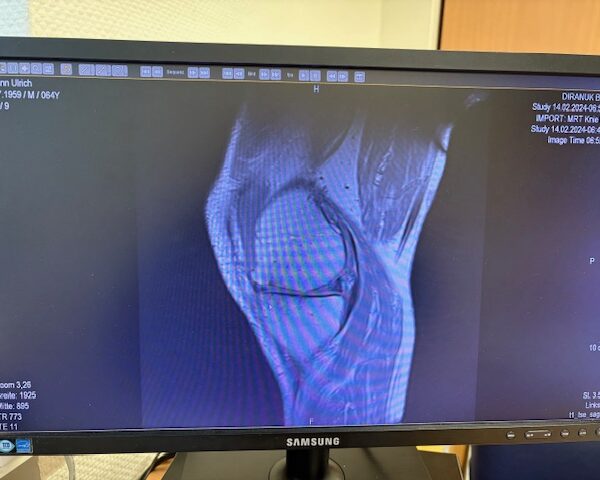

Στον ασθενή τα εμφυτεύματα που χρησιμοποιήθηκαν είναι της εταιρείας Zimmer-Biomet Persona Μηριαίο μέγεθος 6, κνημιαίο μέγεθος Η και ενθέμα (inlay) Η li. 8mm.

Πραγματοποιήθηκε απεικόνιση και ψηφιακός σχεδιασμός της επέμβασης, ώστε να προσδιοριστεί με ακρίβεια το μέγεθος και η θέση των προθέσεων. Ο στόχος ήταν να αποκατασταθεί η φυσιολογική μηχανική του γόνατος, διατηρώντας ανέπαφα τα υγιή τμήματα της άρθρωσης, τους συνδέσμους και τους γύρω μυς.